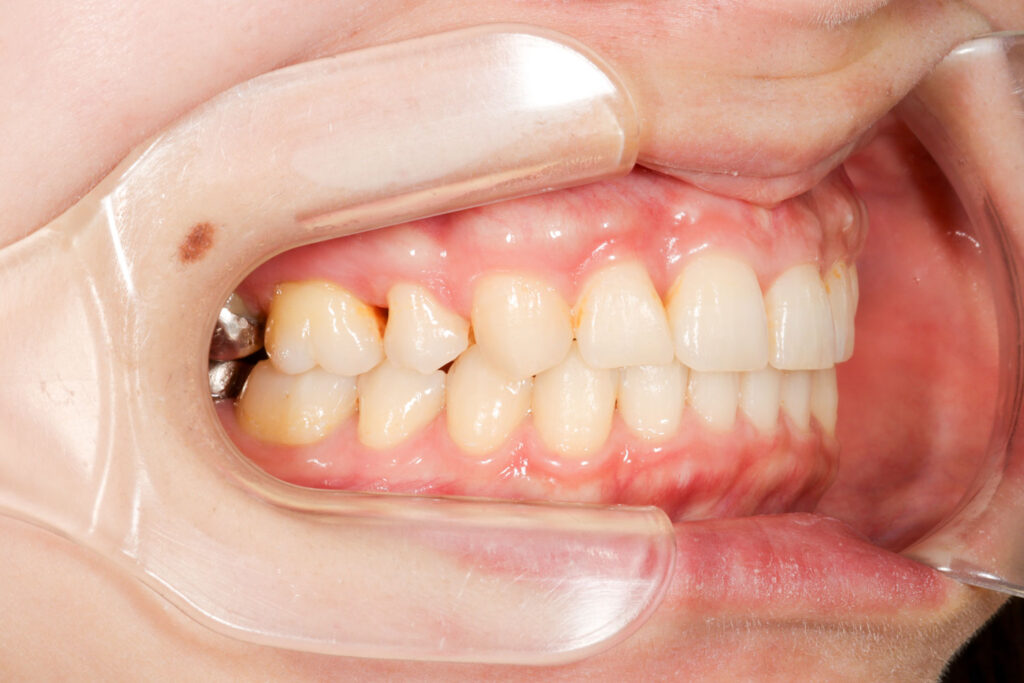

Before

After

年齢 10代

治療装置 上は裏側の矯正装置(フルリンガル)

治療内容 非抜歯

治療期間 2年8か月

リスク 歯の移動に伴う痛み、歯肉退縮、歯根吸収、歯肉炎、虫歯

主訴 ガタガタと隙間が気になる

症状 叢生と正中離開

治療回数 36回程度

総額費用 140万円程度